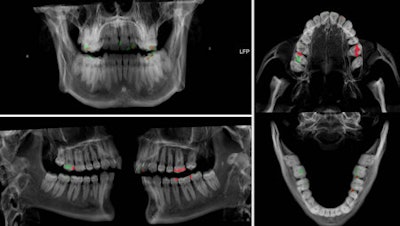

A case in point is the visualization of dental fillings. Dental x-ray plays a key role alongside DNA in identifying human remains whether in mass fatalities or single incidents when bodies have undergone alteration after death. Up to 80% of postmortem identification in the wake of the Asian tsunami in 2004 was based on dental status. Ultrahigh-resolution dual-source CT with extended CT scale has proved to reduce streak-induced artifacts and distinguish between fillings, whether composite, amalgam, ceramic, or temporary fillings, based on radiopacity in Hounsfield units, their size, and location.

Cross section of investigated teeth and Hounsfield unit profile along a measurement indicated as a white line in the molar. All images courtesy of Dr. Christian Jackowski.

A volume rendering preset suggestion to apply for dental CT data based on the investigated teeth. White for physiological dental structures such as dentine and enamel. Low opaque composite fillings are shown in green whereas high opaque composite fillings are shown in red.Using a Siemens Healthcare Definition Flash, Jackowski has dedicated the past year of ongoing research to the development of a dual-energy application of more than 30,000 Hounsfield units and a software tool to analyze the data obtained to further characterize filling materials. This development could have implications for other areas of postmortem imaging such as bullet characterization.